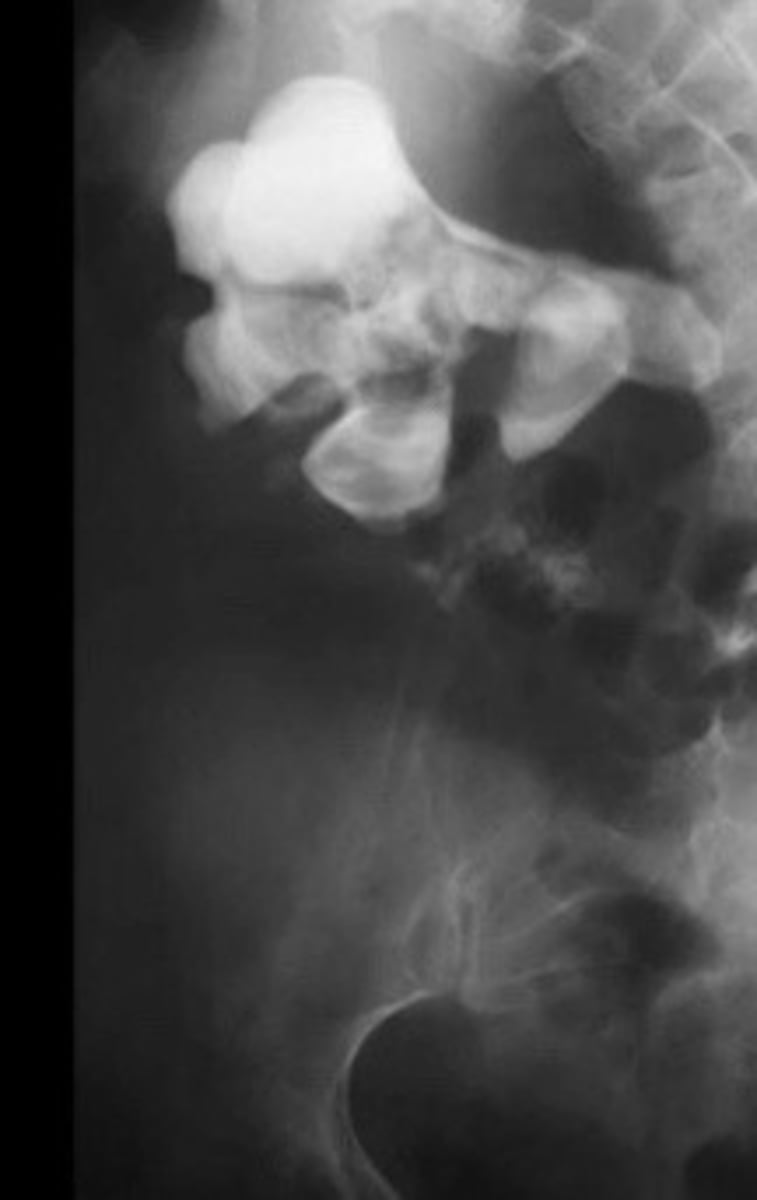

X-ray of staghorn calculi

What does this image show

<p>What does this image show</p>

48